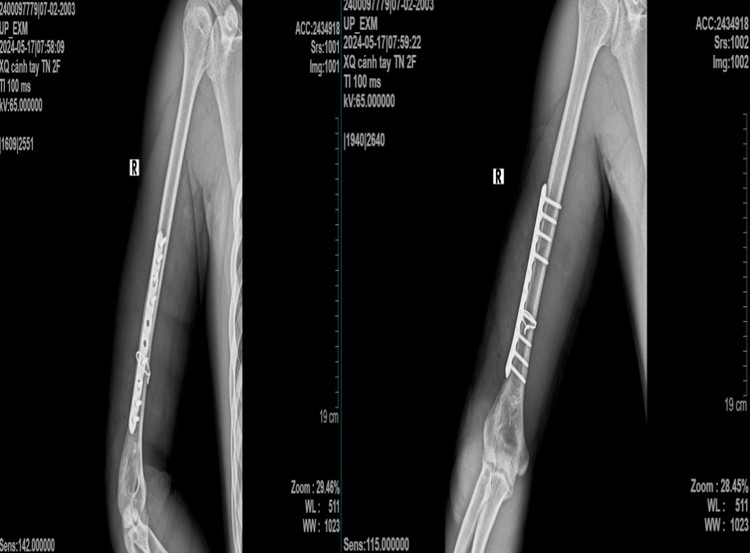

Ngày 14/5/2024, khi đang chơi vật tay cùng bạn thì đột nhiên thấy tiếng “cục” và sau đó đau chói, biến dạng, mất vận động cánh tay phải. Sau khi nhập viện, bệnh nhân được chẩn đoán: Gãy kín xương cánh tay phải không liệt quay, chỉ định phẫu thuật kết hợp xương nẹp vít.

Sau phẫu thuật kết hợp xương nẹp vít, người bệnh được chụp x-quang kiểm tra sau mổ, giải phẫu xương cánh tay được phục hồi, người bệnh ra viện sau 4 ngày.

| Hình ảnh x-quang sau phẫu thuật của bệnh nhân - Ảnh: BVCC |